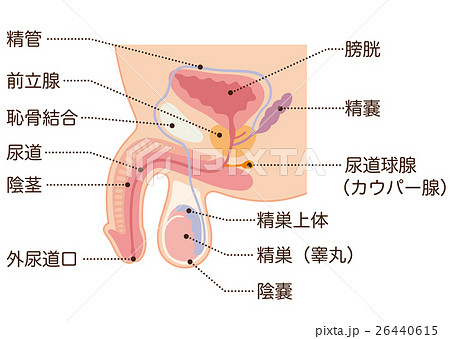

男性生殖器断面人体図 名称付き メディカルイラスト図鑑 無料の医療 美容素材集

男性生殖器断面人体図 名称付き メディカルイラスト図鑑 無料の医療 美容素材集

男性生殖器 断面図 Stock Illustration Adobe Stock

男性生殖器 断面図のイラスト素材

男性生殖器 断面図のイラスト素材

前立腺癌の検査